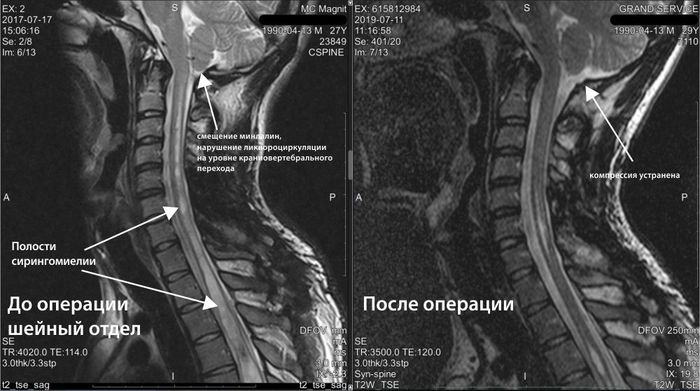

Во время операции выяснилось: у Оли врожденная аномалия сосудов — артериовенозная мальформация. Именно она стала причиной катастрофы. После операции девочка провела три дня в коме, а после — две с половиной недели в реанимации.

Но оставалась главная угроза: мальформация сосудов имела аномальные размеры, поэтому Оле сделали ещё одну операцию. Она прошла успешно. Но в феврале этого года семью ждал новый удар: у Оли случился эпилептический приступ. Оказалось: новая мальформация. В конце марта Оле сделали третью операцию. И после неё Оля снова растеряла все навыки, которые с таким трудом смогла вернуть.